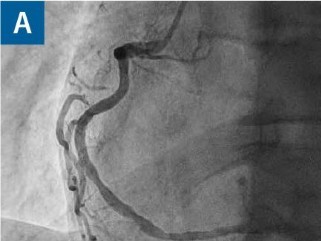

Junger Sportler mit Herzproblemen unter Belastung — wie lautet Ihre Diagnose?

Ein 37-jähriger Mann stellt sich zur weiteren Abklärung thorakaler Beschwerden vor. Er ist schlank, sportlich und raucht 2-4 Zigaretten am Tag. Puls, Blutdruck und das Aufnahme-EKG sind unauffällig — nicht aber die Koronarangiografie.

DGIM Podcast-Reihe - Frailty/© (M) David L / peopleimages.com / Stock.adobe.com (Symbolbild mit Fotomodell), Junge Frau misst Blutdruck bei älterer Frau/© CasarsaGuru / Getty Images / iStock (Symbolbild mit Fotomodellen), Ältere Dame nimmt Tabletten ein/© Satjawat / stock.adobe.com (Symbolbild mit Fotomodell), Älterer Mann schaut kritisch auf Tabletten/© Mediteraneo / stock.adobe.com (Symbolbild mit Fotomodell), Blutabnahme/© Grafvision / stock.adobe.com (Symbolbild mit Fotomodellen), Frau auf einem Laufband mit Elektroden am Oberkörper/© technotr / Getty Images / iStock (Symbolbild mit Fotomodell), Ältere Dame in Reha/© W PRODUCTION / stock.adobe.com (Symbolbild mit Fotomodellen), Arzt berät Patienten zu Pillen/© crizzystudio / stock.adobe.com (Symbolbild mit Fotomodell), Frau misst Blutdruck/© Microgen / stock.adobe.com (Symbolbild mit Fotomodell), Blutabnahme bei einem Jungen/© Kalim / Stock.adobe.com (Symbolbild mit Fotomodellen), CT-Koronarangiographie eines Patienten mit Plaque im RIVA/© Springer Medizin, Junge Patientin im Gespräch mit einer Ärztin/© FatCamera / Getty Images / iStock (Symbolbild mit Fotomodellen), Alte Frau hält Sportbälle in Fitnessstudio hoch/© Robert Kneschke / stock.adobe.com (Symbolbild mit Fotomodell), Lipidprofil/© gamjai / stock.adobe.com, Koronarangiografie der Herzkranzarterien/© S. Dörr, Bild einer Endokarditis der Mitralklappe/© C. Stremmel, Search Icon, Person hält Tablette und Glas/© bilderstoeckchen / stock.adobe.com (Symbolbild mit Fotomodell), Ultraschall bei einem älteren Patienten/© Alex Potemkin / Getty Images / iStock (Symbolbild mit Fotomodellen), EKG befunden mit System - EKG Essential/© Springer Medizin Verlag GmbH